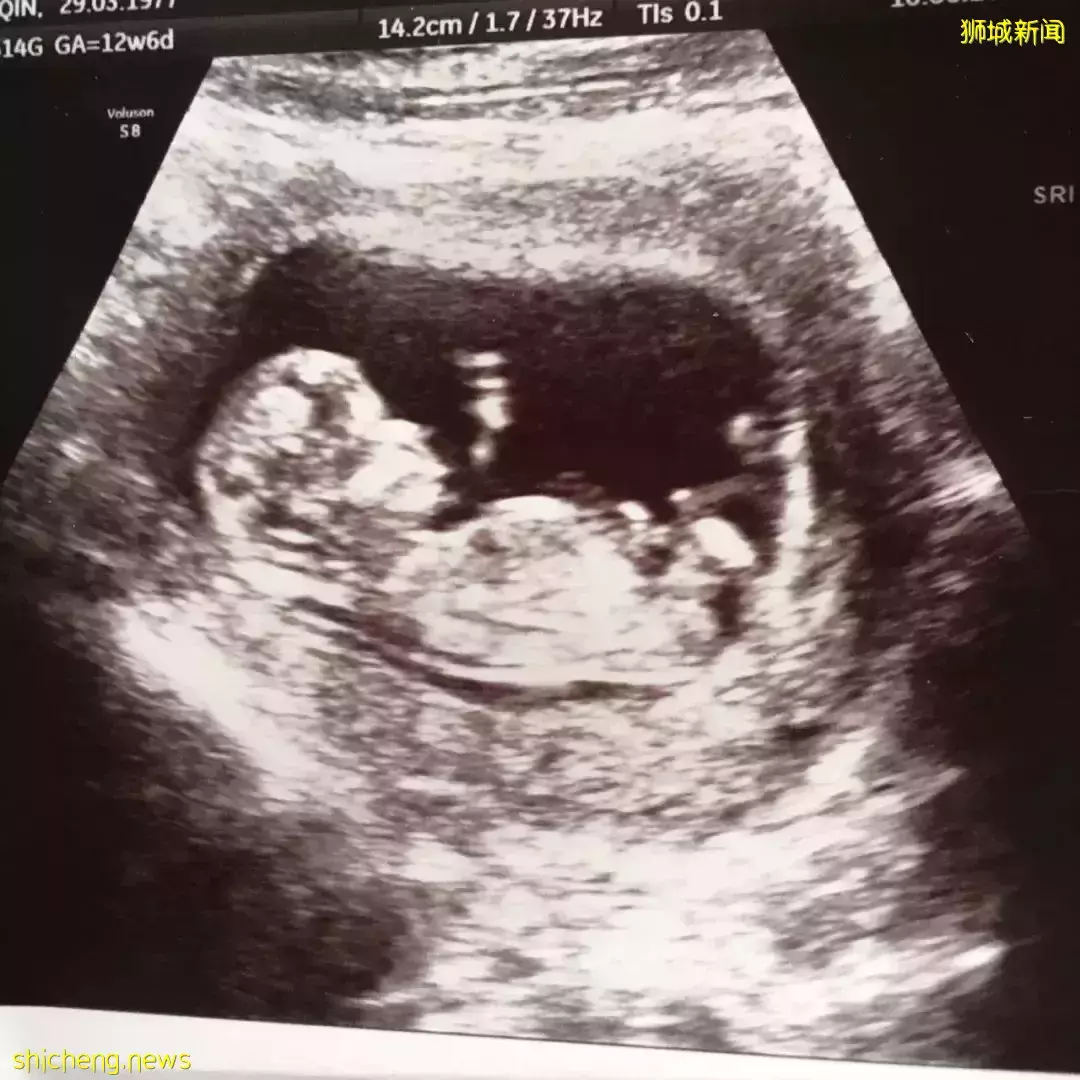

到了SGH,在O&G Centre先照了B超,闭着眼睛爬上床,扫描的时候睁眼看到胎儿心跳一闪一闪地。我心想:“幸好,宝宝还在!”